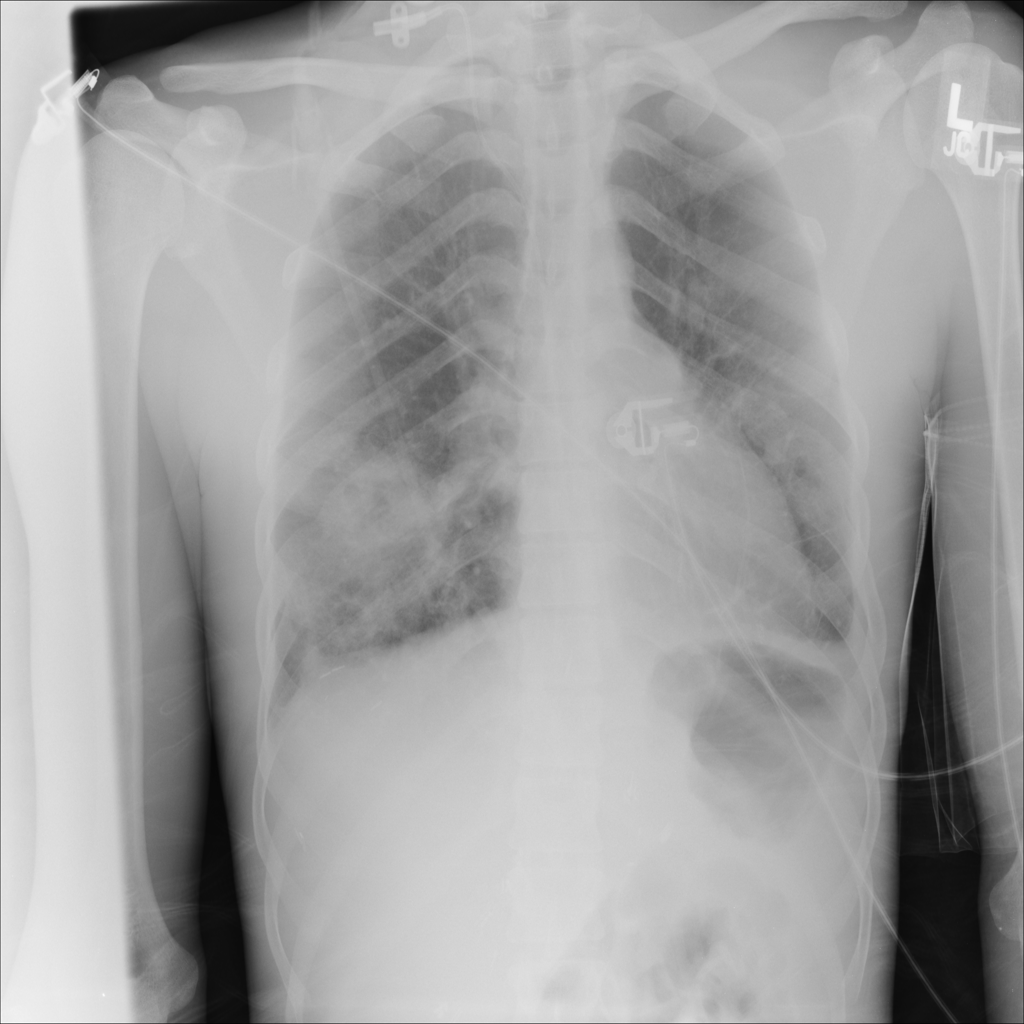

Mass

A mass is a larger focal opacity or lesion seen on the image. It is a descriptive finding that can have several causes and usually needs more imaging or clinical context to characterize.

PAT-4639 · IMG-024Mass

PAT-4639 · IMG-024

AP